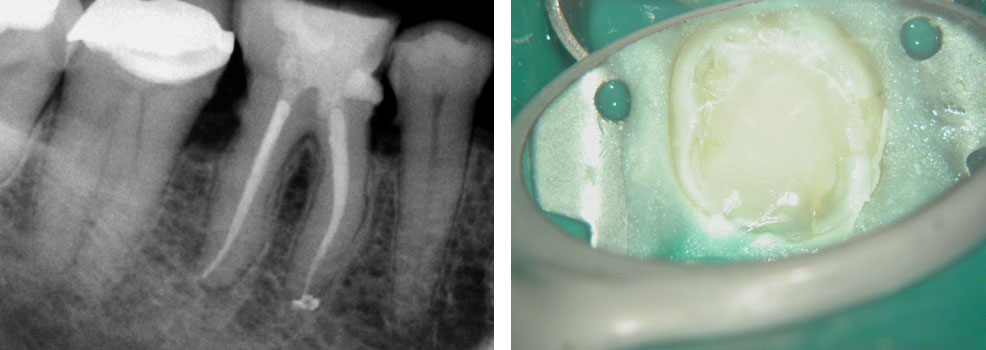

History of persistent swelling in the maxillay first molar despit repeated calcium hydroxide dressings. Patient has undergone multiple “open” and “closed dressings”.

Red arrow shows calcification covering the MB2. Removal of this calcification with ultrasonics reveals the missed MB2(yellow arrow)

5 canals cleaned, shaped and obturated after 10 days of calcium hydroxide. MB1 and MB2 had seperate portals of exit. DB2 merged intoDB1. Palatal two portals of exit.